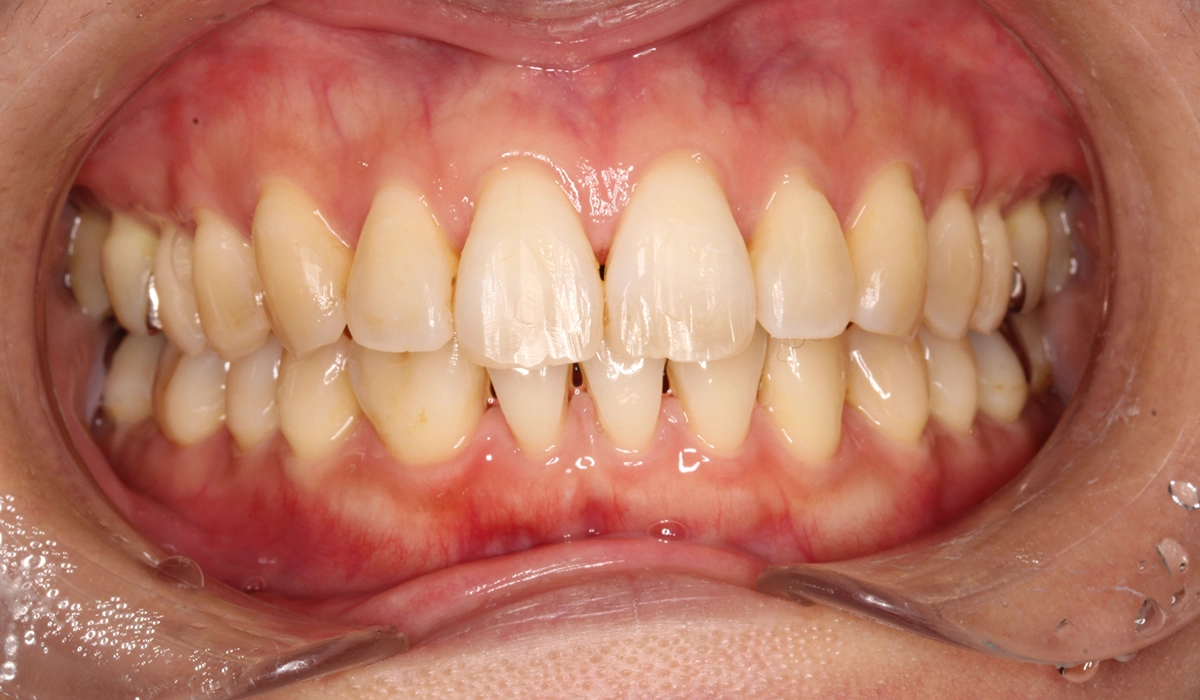

術前:正面

術後:正面